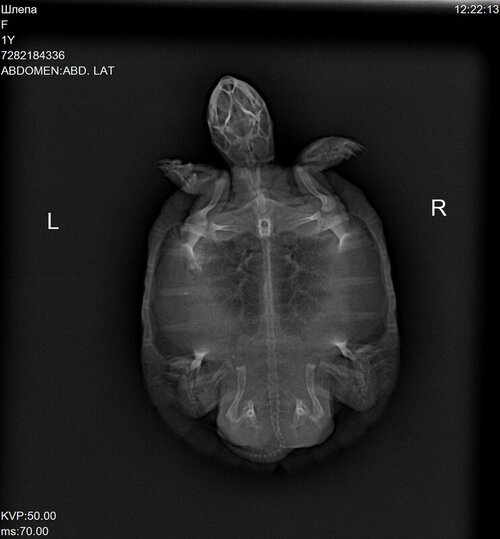

Врач Шевченко Матвей Олегович, вет.клиника Прайд: сделал рентген, сказал, что что-то есть в желудке и что-то давит на лёгкие, заметил розоватый цвет на лапах и пластрон - сказал, что возможно воспаление или проблемы с почками

7282184336_1.thumb.JPG.d04b396017daf9699fd013ff158ea415.JPG7282184336_2.thumb.JPG.daf96f8221ee11b4a2738eae8e3638c0.JPG

В Вашем случае нужно определять требуется операция или нет, есть непроходимость или трава движется по жкт. По-хорошему Вам должны были делать рентген с контрастом и интервальные снимки, а не гадать что там пережимает лёгкие. Потому что рвота эспумизаном это либо Вы неправильно вводите катетер и не попадаете в желудок, либо движения по жкт нет и эспумизану просто некуда деваться.

@moth Черепашка покакала, скушала один кусочек Серы и поклевала сепию. Свозила в Котонаи, там ее прощупали, сделали рентген и взяли кровь на биохимический анализ. В кишечнике есть инородные кусочки, но сказали, что непроходимости нет. Вкололи Элеовит 0,1 мл. Сказали пока ничего не делать и ждать анализов крови